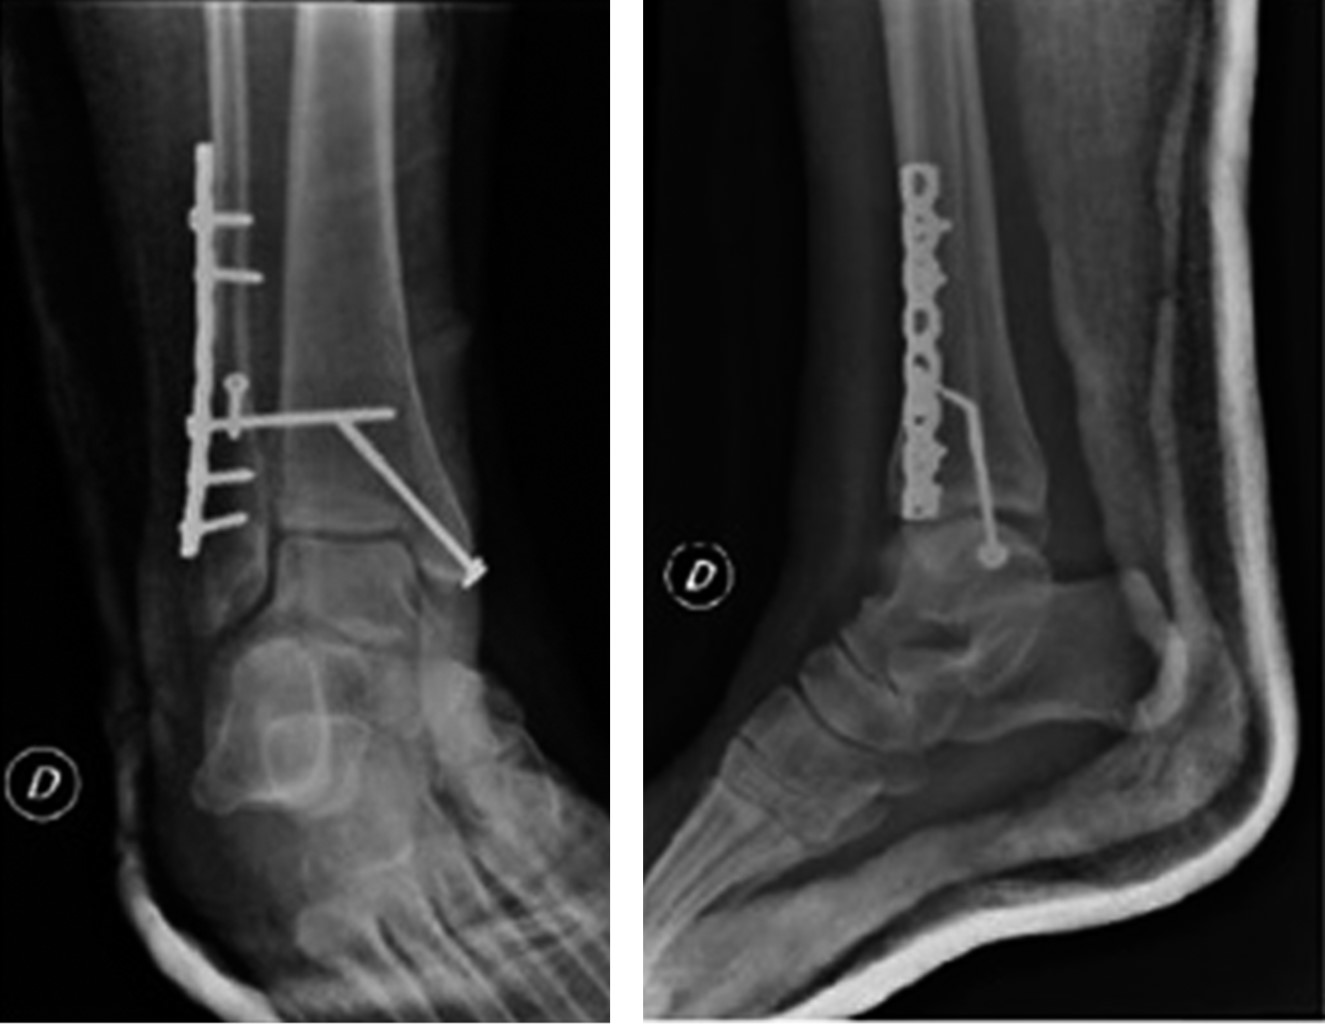

Después se realizó procedimiento quirúrgico con reducción y osteosíntesis de maléolo lateral con tornillo interfragmentario y placa de reconstrucción de huesos planos de ocho orificios; maléolo medial con tornillo rosca parcial con arandela; reducción de sindesmosis y colocación de tornillo transindesmal a través de placa. Inmovilización con férula de yeso. Paciente tolera la cirugía sin complicaciones con alta sanatorial al día siguiente.

El primer control postquirúrgico se realizó a los seis días de la cirugía, donde se constatan heridas con buena evolución sin signos de infección ni flogosis (Figura 3). La paciente no presentaba dolor pero sí intenso edema de miembro inferior con pulsos periféricos y sensibilidad conservada, por lo que se solicita ecografía Doppler que manifiesta signos en favor de trombosis venosa aguda focal y segmentaria. Aquel estudio se informó de manera errónea, ya que lo ubicaba en topografía de vena tibial posterior, sin signos de recanalización. Se modifica medicación anticoagulante: rivaroxabán 15 mg cada 12 horas y se inmoviliza con bota corta de yeso.

Figura 2